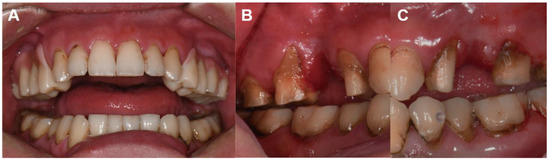

2. Case Report